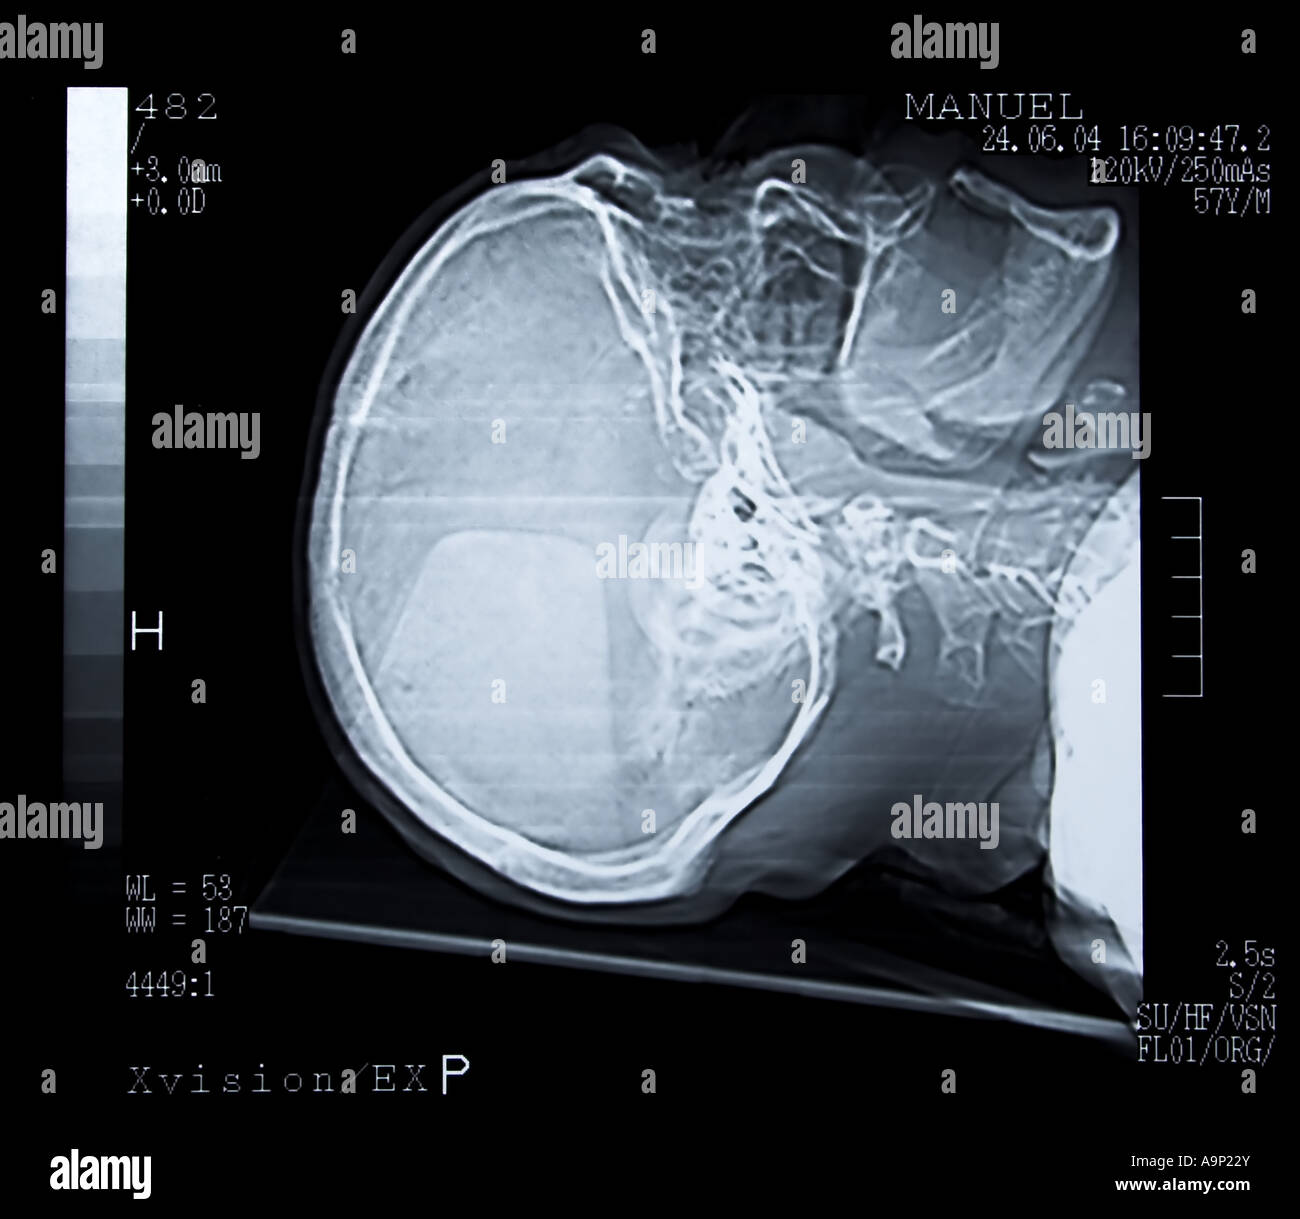

Tomodensitométrie cérébrale Banque D'Imageshttps://www.alamyimages.fr/image-license-details/?v=1https://www.alamyimages.fr/photo-image-tomodensitometrie-cerebrale-12412994.html

Tomodensitométrie cérébrale Banque D'Imageshttps://www.alamyimages.fr/image-license-details/?v=1https://www.alamyimages.fr/photo-image-tomodensitometrie-cerebrale-12412994.htmlRFA9P22Y–Tomodensitométrie cérébrale